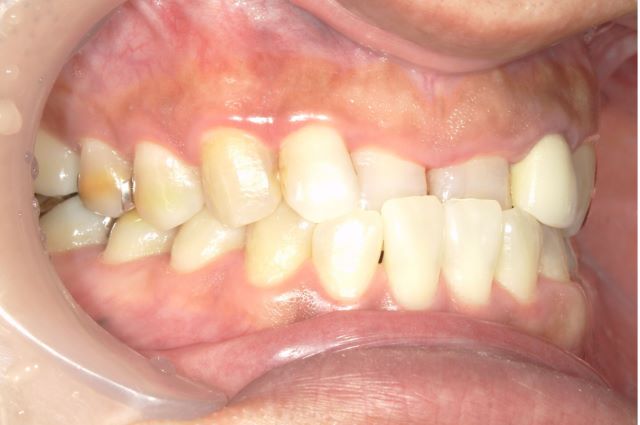

治療前

治療後

デコボコ歯並びも通院2回でこのように治ります。ワイヤー矯正では歯の色までは治せません。この症例について、詳しくはこちらをご覧ください。